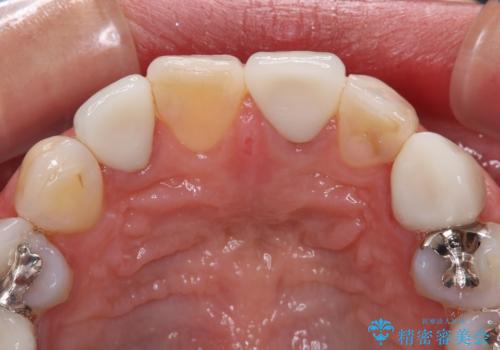

途中通院されなかった時期が何度かあったため、初診から4年以上の年月がかかりましたが、比較的スムーズに治療を進めることができました。

下顎前歯の歯列を整えたことで、上顎前歯の咬み合わせが安定し、自然な口元に仕上げることができました。